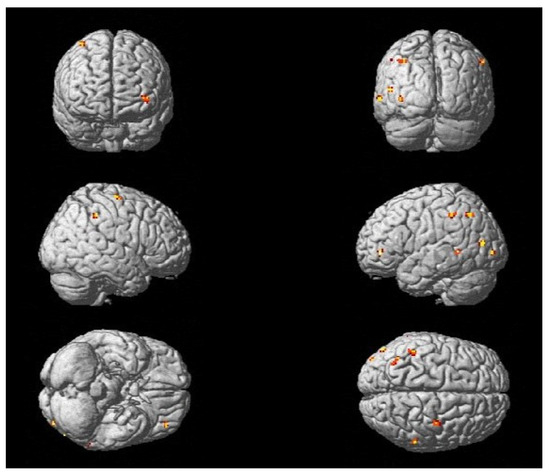

3.1. Utility of Chosen fMRI Paradigms in Acute Stroke Patients with Ataxic Symptoms